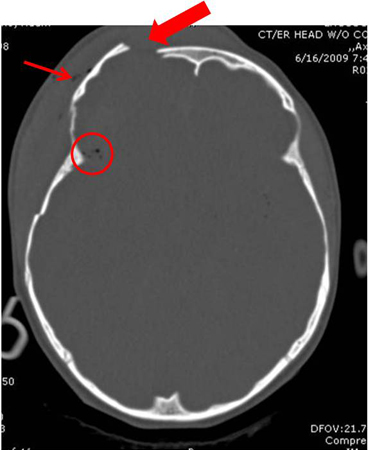

- fratura aberta

- discrepância palpável no contorno do osso